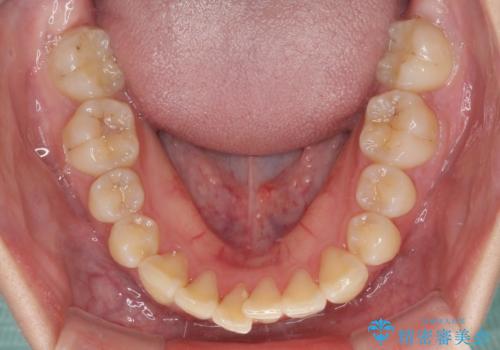

- コンポジットレジンによる治療で継ぎ接ぎだらけになってしまった前歯を綺麗にしたいとのことで来院された患者様です。

必要に応じて根管治療を行い、前歯6歯をオールセラミッククラウンで補綴することとしました。

治療途中に出産を迎えるため、下顎前歯のデコボコを部分矯正で改善し、上下前歯を綺麗に仕上げることとしました。